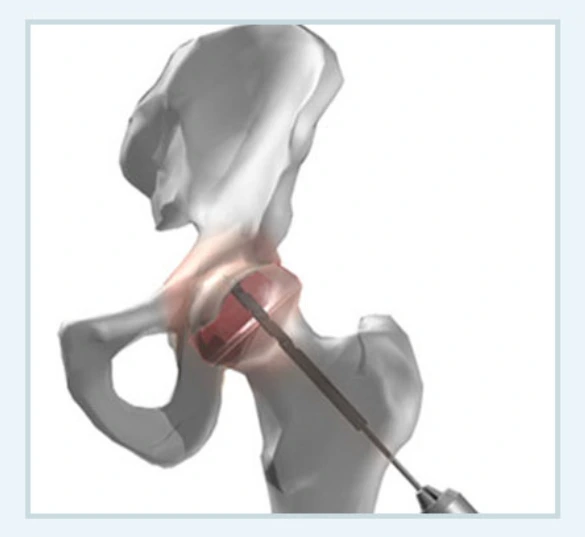

중심감압술

환자의 관절을 그대로 보존하는 치료로 수강 내 압력을 감소시켜 혈관의 재생을 도모하는 치료입니다. 심각한 관절염으로의 진행을 방지할 수 있지만 대퇴골두가 무너지기 전에 치료를 해야 효과적이에요.

중심감압술.PNG